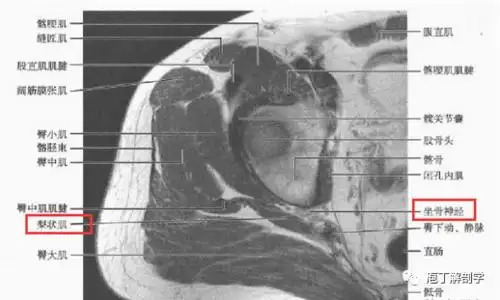

3,梨状肌周围断层解剖2,梨状肌周围结构坐骨神经是人体最粗大的神经